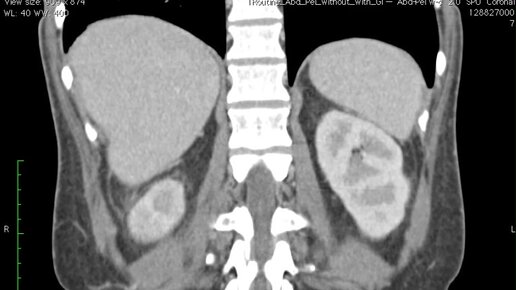

Что покажут снимки КТ почек (видео)